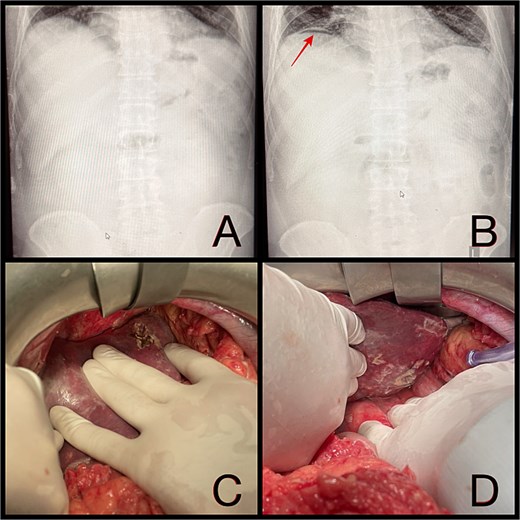

Intraoperatively, a ruptured liver abscess in segment II was found, perforating both the diaphragmatic and visceral hepatic surfaces. There was purulent discharge into the peritoneal cavity, predominantly in the upper abdomen. No gastrointestinal perforation was identified. Abdominal lavage, liver biopsy, and drainage were performed, followed by laparostomy (Fig. 1).

(A and B) Abdominal radiographs showing progression from no free gas (A) to a crescent of pneumoperitoneum beneath the right hemidiaphragm (B, arrow) within 2 hr. (C and D) Intraoperative findings of a ruptured pyogenic liver abscess in segment II, perforating both the diaphragmatic and visceral hepatic surfaces.